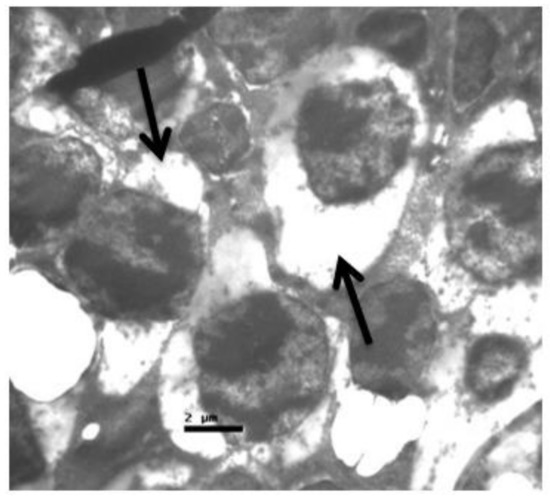

2.1. Group C

2.2. Group V

2.3. Group M